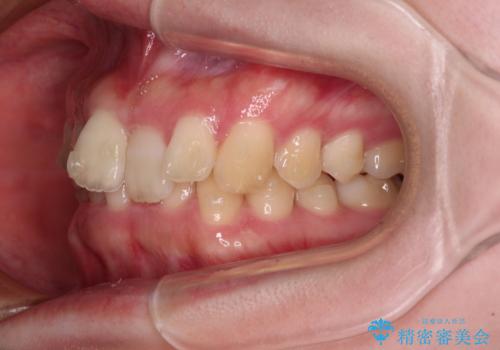

奥歯の咬み合わせを見ると、片方は上顎が下顎に対して相対的に前方にあり、他方は交叉した咬合の状態でした。

咬み合わせを改善するためには、上顎臼歯を後方に移動させた咬み合わせにする必要があります。

インビザライン単体で改善することも可能ですが、ディープバイトのためインビザライン単体で達成する可能性が低いと考えられたため、カリエール・ディスタライザーという補助装置を併用して、より確実性を上げることとしました。

カリエール・ディスタライザーを使用している期間、反対側はワイヤー矯正により叢生を解消していくこととしました。

奥歯の咬み合わせを改善しながら、並行してインビザラインで歯列を整えることとしました。